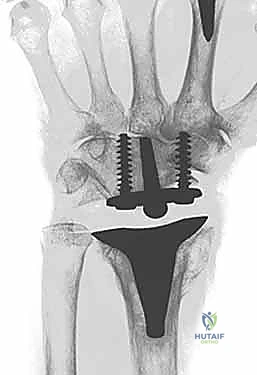

6. تثبيت المفصل الصناعي النهائي

يتكون المفصل الصناعي من جزأين رئيسيين: الجذع الكعبري (الذي يُزرع في عظمة الكعبرة في الساعد) والجذع الرسغي (الذي يُزرع في عظمة المشط الثالثة في اليد). يتم تثبيت هذه الأجزاء إما باستخدام الإسمنت العظمي الطبي، أو عن طريق الانحشار الميكانيكي الدقيق (Press-fit) الذي يسمح بنمو العظم داخل المفصل الصناعي. بين هذين الجزأين المعدنيين، توضع قطعة بلاستيكية عالية الجودة تعمل كغضروف صناعي يسمح بالحركة السلسة.